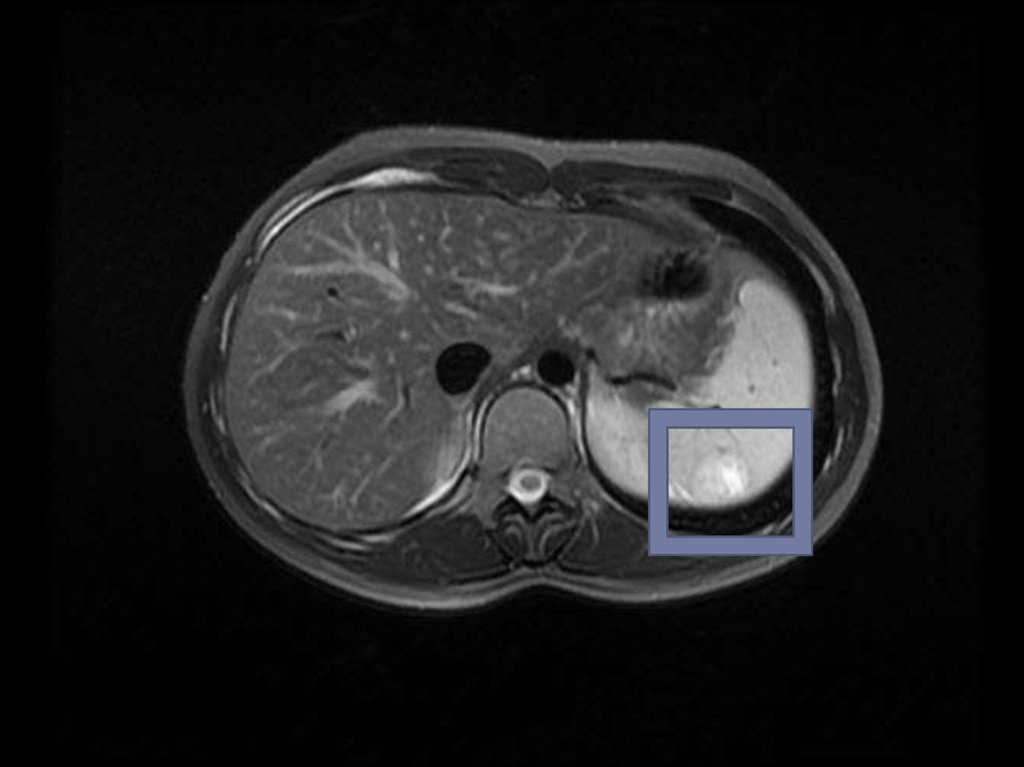

15. По калибру селезеночная вена превышает артерию в 1.5-2 раза